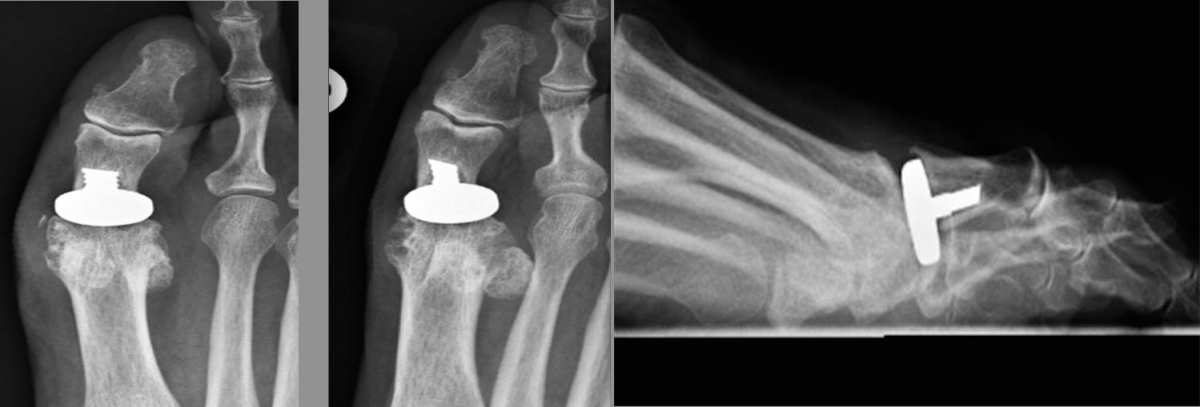

This led to the development of the locking compression plate, which has the ability to preserve the blood supply to bone by reducing periosteal stripping. The traditional plating techniques provided stability by compressing the plate to the bone surface with the screws achieving bicortical purchase as the second point of fixation. However, locking compression plate technology features unicortical locking screws that can be an “internal fixator” that can act as a bridge over compromised bone.8

One of the benefits of locking plates is their ability to be “bridge plates,” whereby they provide excellent axial and angular stability, preserve fragmentary blood supply, and reduce the risk of loss of reduction. Indeed, surgeons do not have to contour these plates anatomically to the bone, and the plates have the potential benefit of providing superior fixation in osteoporotic bone. Indications for the use of locking plates include diaphyseal/metaphyseal fractures in osteoporotic bone, multifragmentary diaphyseal/metaphyseal fractures, osteotomies in at-risk patients (poor bone stock, revisions, etc.), articular fractures, segmental fractures with multiple patterns, and any combination of the above.9

Another advancement in the development of locking plate technology is the addition of polyaxial or variable axial screw holes in the plate. This becomes extremely valuable when a surgeon is addressing a periarticular fracture, especially one that involves significant comminution or damage to the soft tissue envelope. These plates were designed to improve angular stability by allowing variable screw trajectory to the plate, thereby increasing the probability that the screw will be able to purchase good bone while avoiding articulating surfaces.